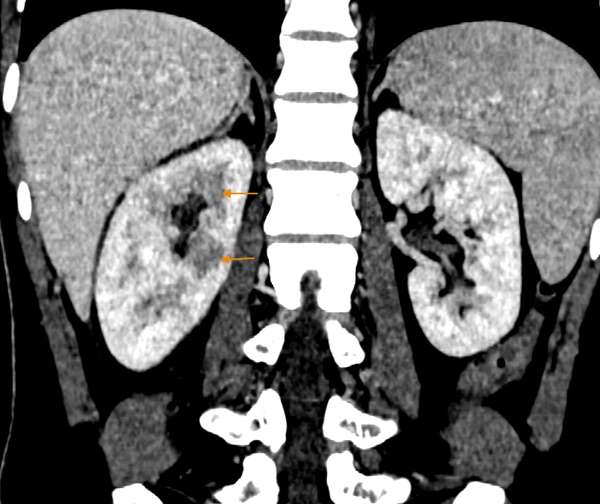

Kết quả khám lâm sàng và các xét nghiệm cần thiết cho thấy chỉ số viêm của bệnh nhân tăng, hình ảnh CT phát hiện dịch tụ quanh thận, nhu mô thận phải không đều, đặc biệt vùng sau bể thận. Bệnh nhân được chẩn đoán mắc viêm thận bể thận cấp tính, cần lập tức nhập viện điều trị nội trú.

Hình ảnh CT của bệnh nhân cho thấy nhu mô thận ngấm thuốc không đều, biểu hiện của viêm thận (Ảnh: BSCC)